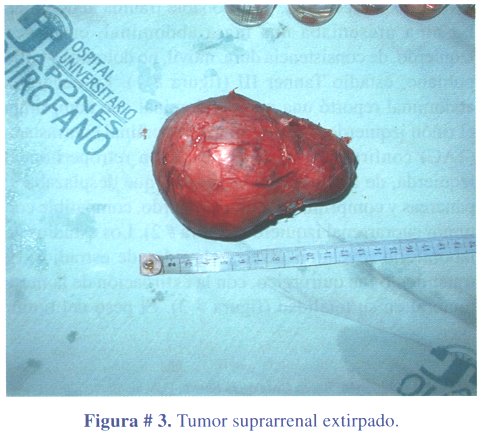

1º caso clínico: niña de 3 años y 6 meses de edad, que acudió a consulta médica por presentar dolor abdominal y vómitos a repetición, por probable trauma abdominal. La niña presentaba una masa abdominal, en flanco izquierdo, de consistencia dura, móvil, no dolorosa y vello pubiano, estadio Tanner III (figura # 1). La ecografía abdominal reportó una masa abdominal que comprimía el riñón izquierdo. La tomografía abdominal contrastada (TAC) confirmó la masa de ubicación retroperitoneal izquierda, de densidad heterogénea y que desplazaba el páncreas y comprimía el riñón izquierdo, compatible con tumor suprarrenal izquierdo (figura # 2). Los estudios de laboratorio revelaron niveles elevados de estradiol. El tratamiento fue quirúrgico, con la extirpación de la masa tumoral en su totalidad (figura # 3). El peso del tumor fue de 300 gramos.

El informe anatomopatológico confirmó tratarse de un adenocarcinoma suprarrenal (figura # 4).